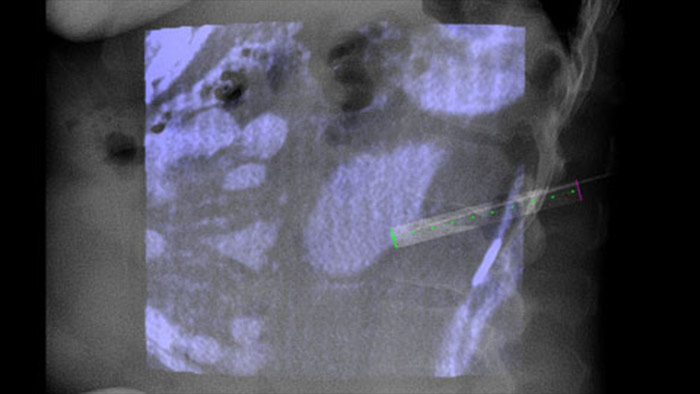

SmartCT Soft Tissue offers a Cone Beam CT (CBCT) acquisition technique augmented with step-by-step guidance, advanced 3D visualisation and measurement tools; all accessible on the touch screen module at table side.

XperGuide provides highly accurate live image guidance of each needle to a targeted position by overlaying pre-planned trajectories with fluoroscopic imaging.3

With CBCT acquire a post-ablation CBCT to demonstrate the extent of tumor coverage and confirm completeness of your treatment.